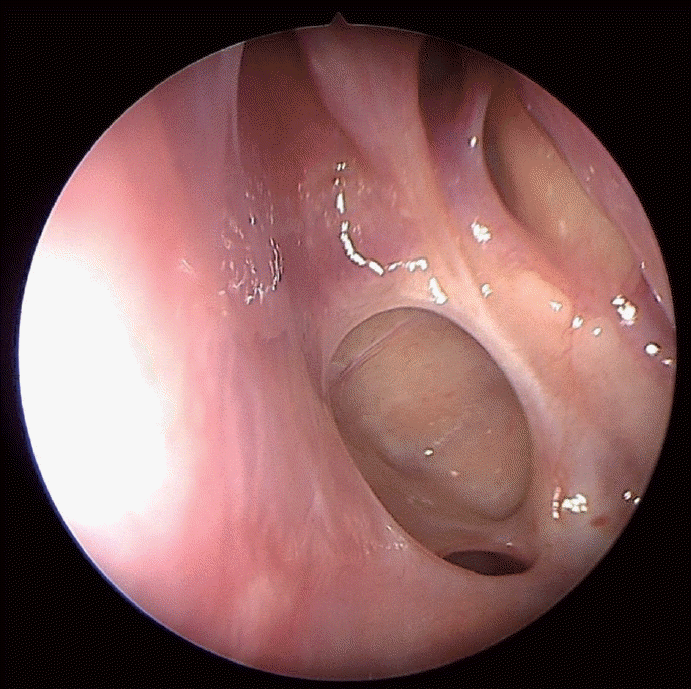

조직병리검사에서 두드러진 핵을 가진 다형성의 큰 종양성 세포가 관찰되었고, T세포 표지자인 CD3, CD45R0을 사용한 면역조직화학 염색에서 국소적 양성을 보였다. 추가적으로 시행한 면역조직화학 염색에서 CD30에 강한 양성을 보였으며 CD20, CD56, cytokeratin, ALK, smooth muscle actin, myoglobin, S100, HMB45에는 음성을 보여 결과를 종합하여 ALK 음성 역형성대세포림프종으로 최종 진단되었다(Fig. 3). 혈액학적 검사상 lactate dehydrogenase는 216 IU/L (106-211 IU/L)였으며 전신 전이 유무 평가 및 병기 결정을 위해 시행한 복부 및 흉부 전산화단층촬영에서 특이소견은 없었고, 양측 골반뼈에서 시행한 골수검사에서 림프종 침윤소견은 없었다. 염색체 검사에서도 특이소견은 없었으나 양전자단층촬영에서 좌측 경부 및 후인두림프절의 전이가 의심되는 소견이 있었다(Fig. 4).

Fig. 3.

Histopathologic features of ALK-negative anaplastic large cell lymphoma. A: The neoplastic cells are large, pleomorphic, and contain prominent nucleoli (hematoxylin and eosin staining, ×200). B: Tumor cells are strongly positive for CD30 with membranous or golgi pattern (immunohistochemical staining, ×200). C-E: Tumor cells are negative for CD20 (C), CD3 (D), and ALK (E) (immunohistochemical staining, ×200). ALK, anaplastic lymphoma kinase.